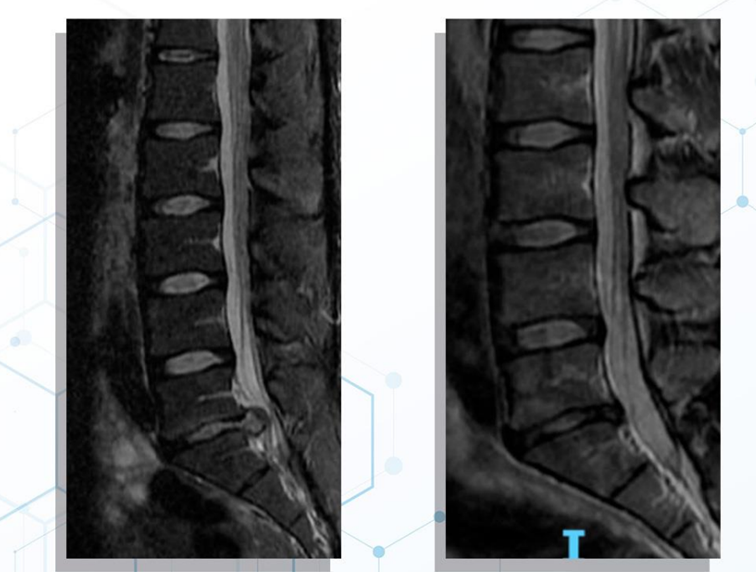

Ilustracja rentgenowska (Figure 3) przedstawia opóźniony zrost złamania kości piszczelowej leczony PEMF. (a) Opóźniony zrost złamania kości piszczelowej zaobserwowano u 65-letniego pacjenta płci męskiej po nastawieniu zamkniętym i unieruchomieniu śródszpikowym 16 tygodni wcześniej. Rozpoczęto leczenie PEMF; (b) Zrost złamania zaobserwowano po 3 miesiącach leczenia.

Ilustracja rentgenowska (Figure 4) przedstawia opóźniony zrost złamania kości udowej leczony PEMF. (a) Leczenie PEMF rozpoczęto u 59-letniego pacjenta płci męskiej, który przeszedł nastawienie i unieruchomienie śródszpikowe 5 miesięcy wcześniej; (b) Radiogramy wykazały postęp do zrostu po 3 miesiącach leczenia, (c) Złamanie zrosło się po 8 miesiącach leczenia.